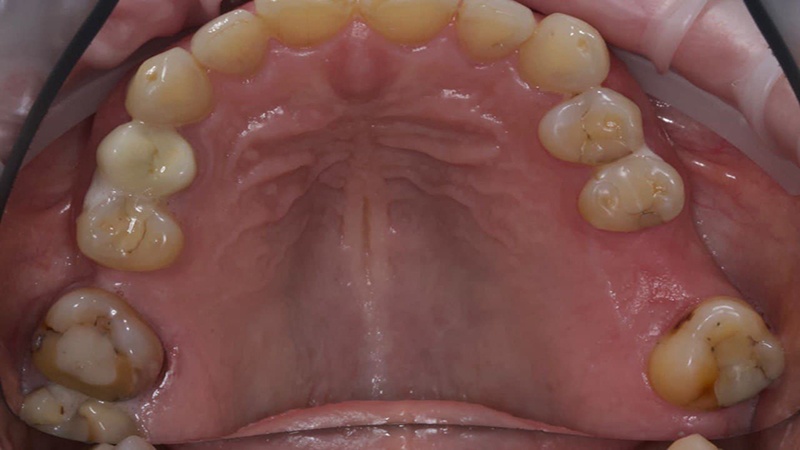

С чем пришла пациентка — нижняя челюсть

Верхняя челюсть

Анамнез: 59 лет, есть ряд проблем, с которыми жить, в общем-то, можно, но лучше бы их решить. То есть часть зубов отсутствует, но не смертельно — улыбаться, разговаривать и есть пока что можно плюс-минус без особой боли. Женщина решает, что пора, и приходит к нам за имплантами. Это частая практика, когда в таком возрасте люди приходят за тотальным протезированием, потому что не хотят бояться стареть. Я такое очень уважаю.

Что у нас было на входе? С правой стороны когда-то были удалены шестой и седьмой зубы, восьмой съехал на место седьмого. С левой — удалён шестой, седьмой с не очень удачно пролеченными каналами, в восьмом огромная полость. Шестой был удалён так давно, что седьмой практически полностью теперь на его месте. Восьмой лежит, не прорезавшийся. Тёмное пятно вокруг седьмого ничего хорошего не говорит, за корнем какая-то проблема локализуется.